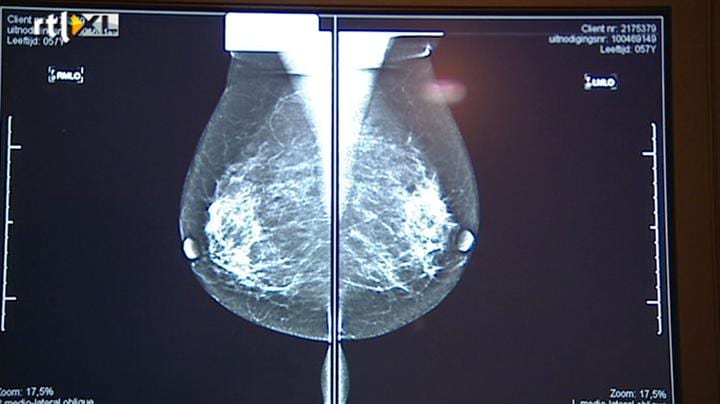

Nu eerst ex-kankerpatienten onder de 50 jaar, die hebben grote problemen met het afsluiten van een hypotheek en levensverzekering. Dat blijkt uit onderzoek van het Integraal Kankercentrum Zuid en de Universiteit Tilburg. Het is voor het eerst dat hiernaar onderzoek is gedaan. Het gaat om zo'n 70 duizend mensen